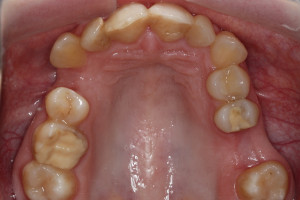

Młoda pacjentka zgłosiła się do naszego gabinetu celem wykonania kompleksowego leczenia zachowawczo-ortodontycznego. Oprócz problemów natury ortodontycznej stwierdzono złą higienę jamy ustnej oraz liczne potrzeby leczenia zachowawczo-endodontycznego. Po wnikliwej analizie telerentgenowskiej oraz analizie modeli zadecydowano o ekstrakcji 2 zębów w łuku dolnym (kła po stronie lewej oraz pierwszego przedtrzonowca po stronie prawej). Plan leczenia obejmował ponadto zamknięcie łuku po brakujących zębach w łuku górnym. Leczenie aktywne trwało 2 lata i 8 miesięcy. W czasie jego trwania pacjentka była regularnie poddawana zabiegom higieny profesjonalnej celem eliminacji zapaleń przyzębia brzeżnego. Po leczeniu aktywnym zastosowano leczenie retencyjne w postaci retainera stałego w żuchwie oraz szyny retencyjnej w łuku górnym.